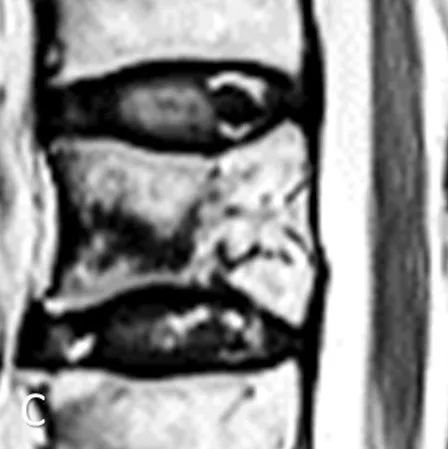

《JBJS》:早期卧床休息对胸腰椎压缩性骨折患者是否有益?

尽管有研究报道影像学结果可预测骨质疏松性椎体骨折(OVF)患者对保守治疗的耐受性,但目前还没有标准化的保守治疗方案。2022年,日本Tsukuba Spine Group分析了和在磁共振成像(MRI)中预后不佳的OVF患者卧床休息对预后的影响,研究结果发表于《JBJS》杂志。该研究于2018年12月至2020年12月期间前瞻性地纳入224名OVF患者。一家医院的108名患者在保守治疗的前2周内进行严格的住院卧床休息,来自另一家医院的116名患者在住院期间没有卧床,医生根据他们的疼痛耐受性指导其尽早进行步行康复。...